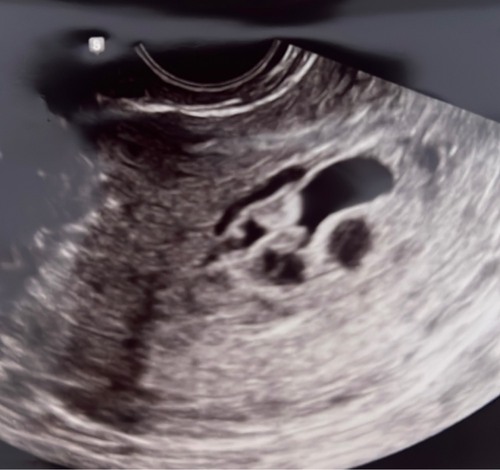

Ik ben sinds april in verwachting en met de medische 13 weken echo is er een afwijkende placenta gezien. De helft van de placenta leek op een gatenkaas en de andere helft leek goed.

De echoscopiste durfde er niks over te zeggen, mijn verloskundige liet het woord mola zwangerschap vallen. We werden doorverwezen naar het ziekenhuis voor verder onderzoek. Al met al bleek het geen mola te zijn omdat het om een goed groeiend kindje gaat.

Na vele onderzoeken blijken het cystes/blaasjes in de placenta te zijn. Ook wel placental mesenchymal dysplasia (PMD) genoemd iets wat heel zeldzaam is en geen bekende oorzaak heeft. Bin PMD bestaat een verhoogd risico op vroeggeboorte, groeivertraging en zwangerschapsvergiftiging waardoor we elke 2 weken naar het ziekenhuis moeten voor een uitgebreide echo/controle.